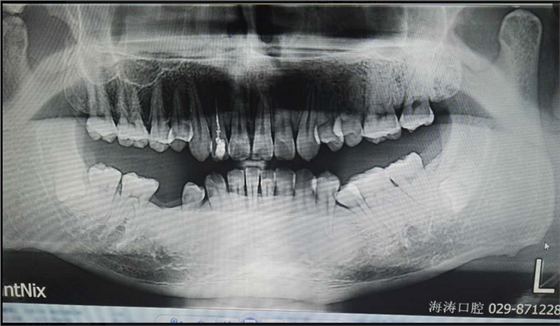

討論四:片子顯示的倒置阻生牙撥牙關(guān)健注意幾點(diǎn),1.翻瓣后去骨部位盡量離7遠(yuǎn)中,別破壞7遠(yuǎn)中骨壁,避免損傷7,以去除8根部的阻力為主。2.暴露阻生牙后,用鉆磨斷部分冠根后,用小骨鑿劈裂冠與根,可避免牙鉆因視野而誤傷神經(jīng)。3.冠根裂開后,先用牙挺挺出根部,然后挺出冠部。